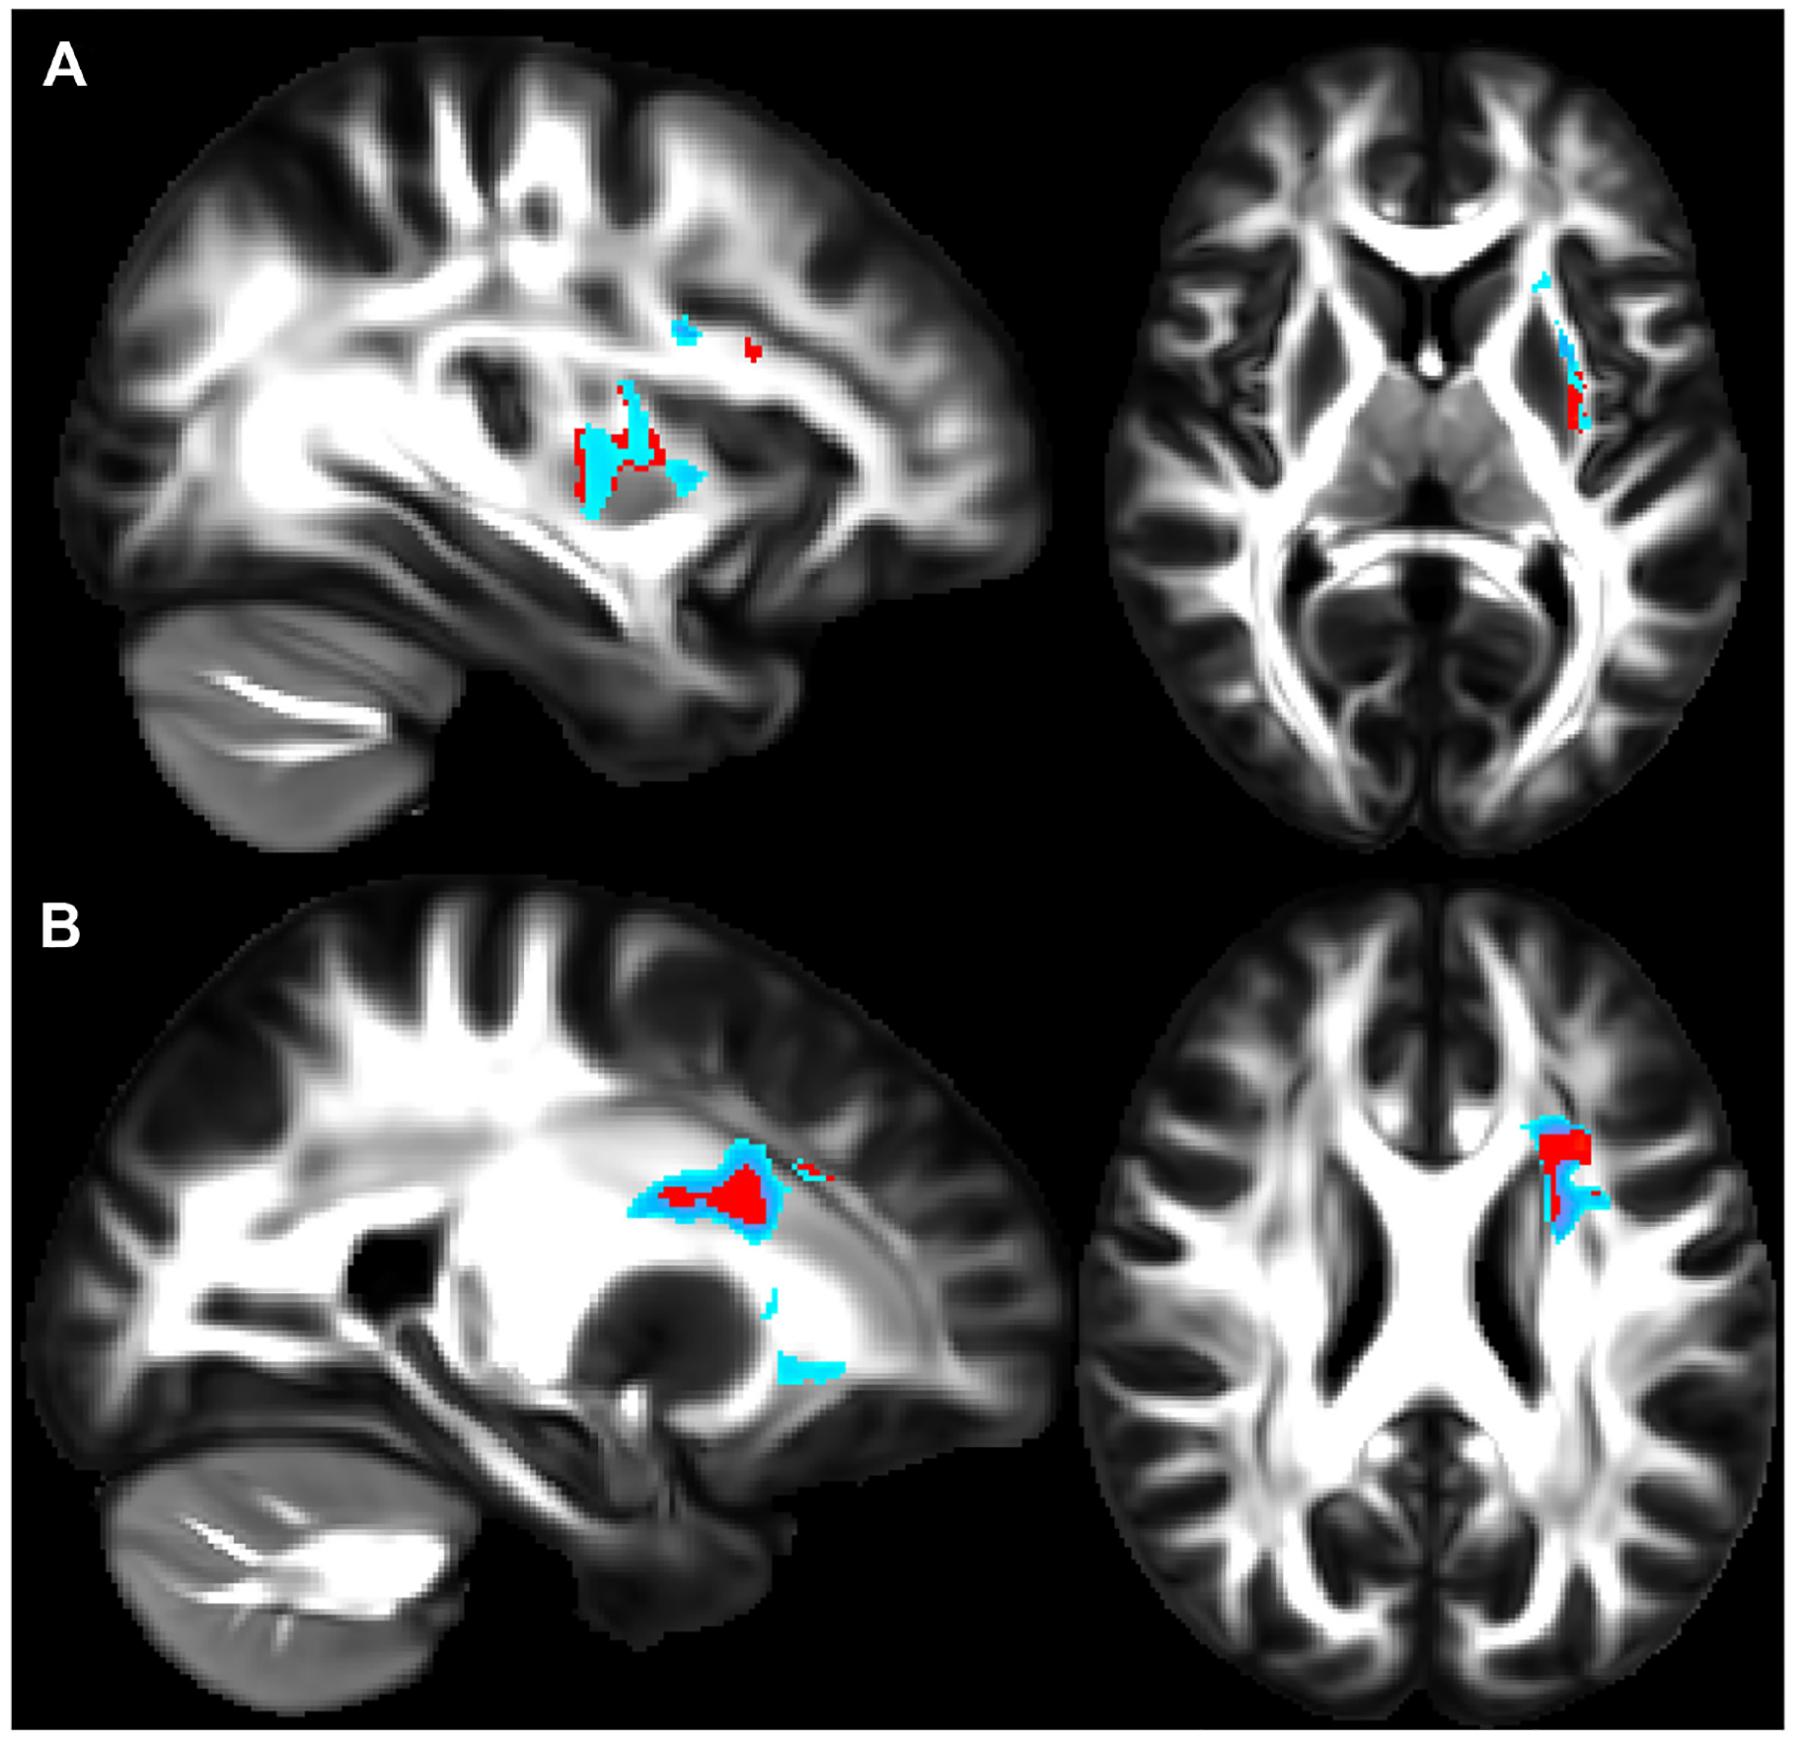

Glucagon-like peptide-1 (GLP-1) is a hormone that regulates blood glucose levels and is produced by the enteroendocrine glands in the large and small intestines in response to the consumption of foods that contain carbohydrates, fats, and proteins. When GLP-1 is secreted, it acts on the pancreas to increase insulin production and secretion, while decreasing pancreatic glucagon secretion in order to lower serum glucose. However, GLP-1 also regulates metabolism through the gut-brain axis. While GLP-1 is primarily produced in the gut and released into the bloodstream, small quantities of it can also be synthesized in distinct areas of neurons located in the hindbrain. Recent studies have proposed that GLP-1 receptor (GLP-1R) agonists (GLP-1RAs) may protect against neuroinflammatory diseases. GLP-1RAs may also be a therapeutic target for asthma as animal models show that these drugs reduce allergen-induced airway inflammation, as the GLP-1R is expressed on lung epithelial and endothelial cells. There is a notable association between insulin resistance and the onset of asthma, particularly among obese people, with this association suggesting that metabolic dysfunction may play a role in asthma development. There is also evidence that there may be a link between asthma pathobiology and neuroinflammation, suggesting that GLP-1 and its analogs may regulate neuroinflammatory pathways that contribute to asthma pathogenesis. Interest is growing, though research remains limited, in how inflammation in the nervous system and lung might be linked. This review will explore how GLP-1R signaling could inhibit interdependent inflammation in both the lung and nervous system. This review will first focus on the inflammation that is known to exist in asthma, then pivot to the current state of neural regulation of asthma, and finally speculate on how GLP-1RA signaling could inhibit both neural and lung inflammation in asthma treatment.